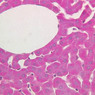

The structure of sinusoids can be studied in the liver (B-29, H&E [10x, 20x, 40x] [10x-labeled, 20x, 40x-labeled]; B-30, H&E [10x, 20x, 40x]; B-35, PAS [10x, 20x, 40x]) where they occur as endothelial tubes between plates of hepatocytes. In the liver, they are channels slightly larger in diameter than red blood cells and the individual lining cells have open spaces between them. The principal difference between sinusoids and capillaries is size, which presumably allows blood to flow more slowly in the larger sinusoids.